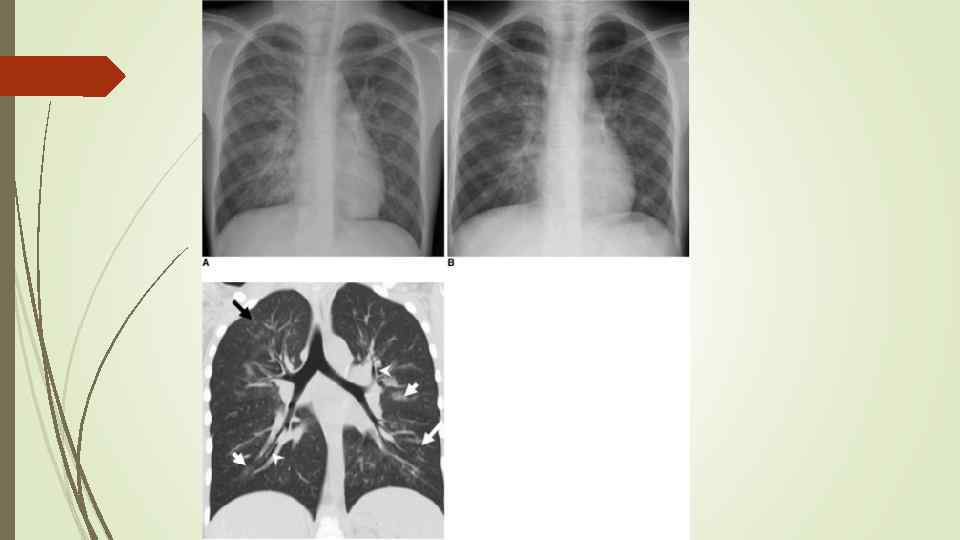

Бронхопневмония Характерно наличие двухсторонних множественных очаговых теней. Контуры очагов нечеткие, интенсивность тени небольшая. Инфильтрация неоднородна. Мелкие, малоинтенсивные очаги не всегда выявляются на снимках. Легочный рисунок усилен на всем протяжении легких. Корни расширены, не структурны. Как правило, отмечается реакция плевры, могут быть и экссудативные плевриты.

Бронхопневмония Характерно наличие двухсторонних множественных очаговых теней. Контуры очагов нечеткие, интенсивность тени небольшая. Инфильтрация неоднородна. Мелкие, малоинтенсивные очаги не всегда выявляются на снимках. Легочный рисунок усилен на всем протяжении легких. Корни расширены, не структурны. Как правило, отмечается реакция плевры, могут быть и экссудативные плевриты.

bronhopneumoni

bronhopneumoni